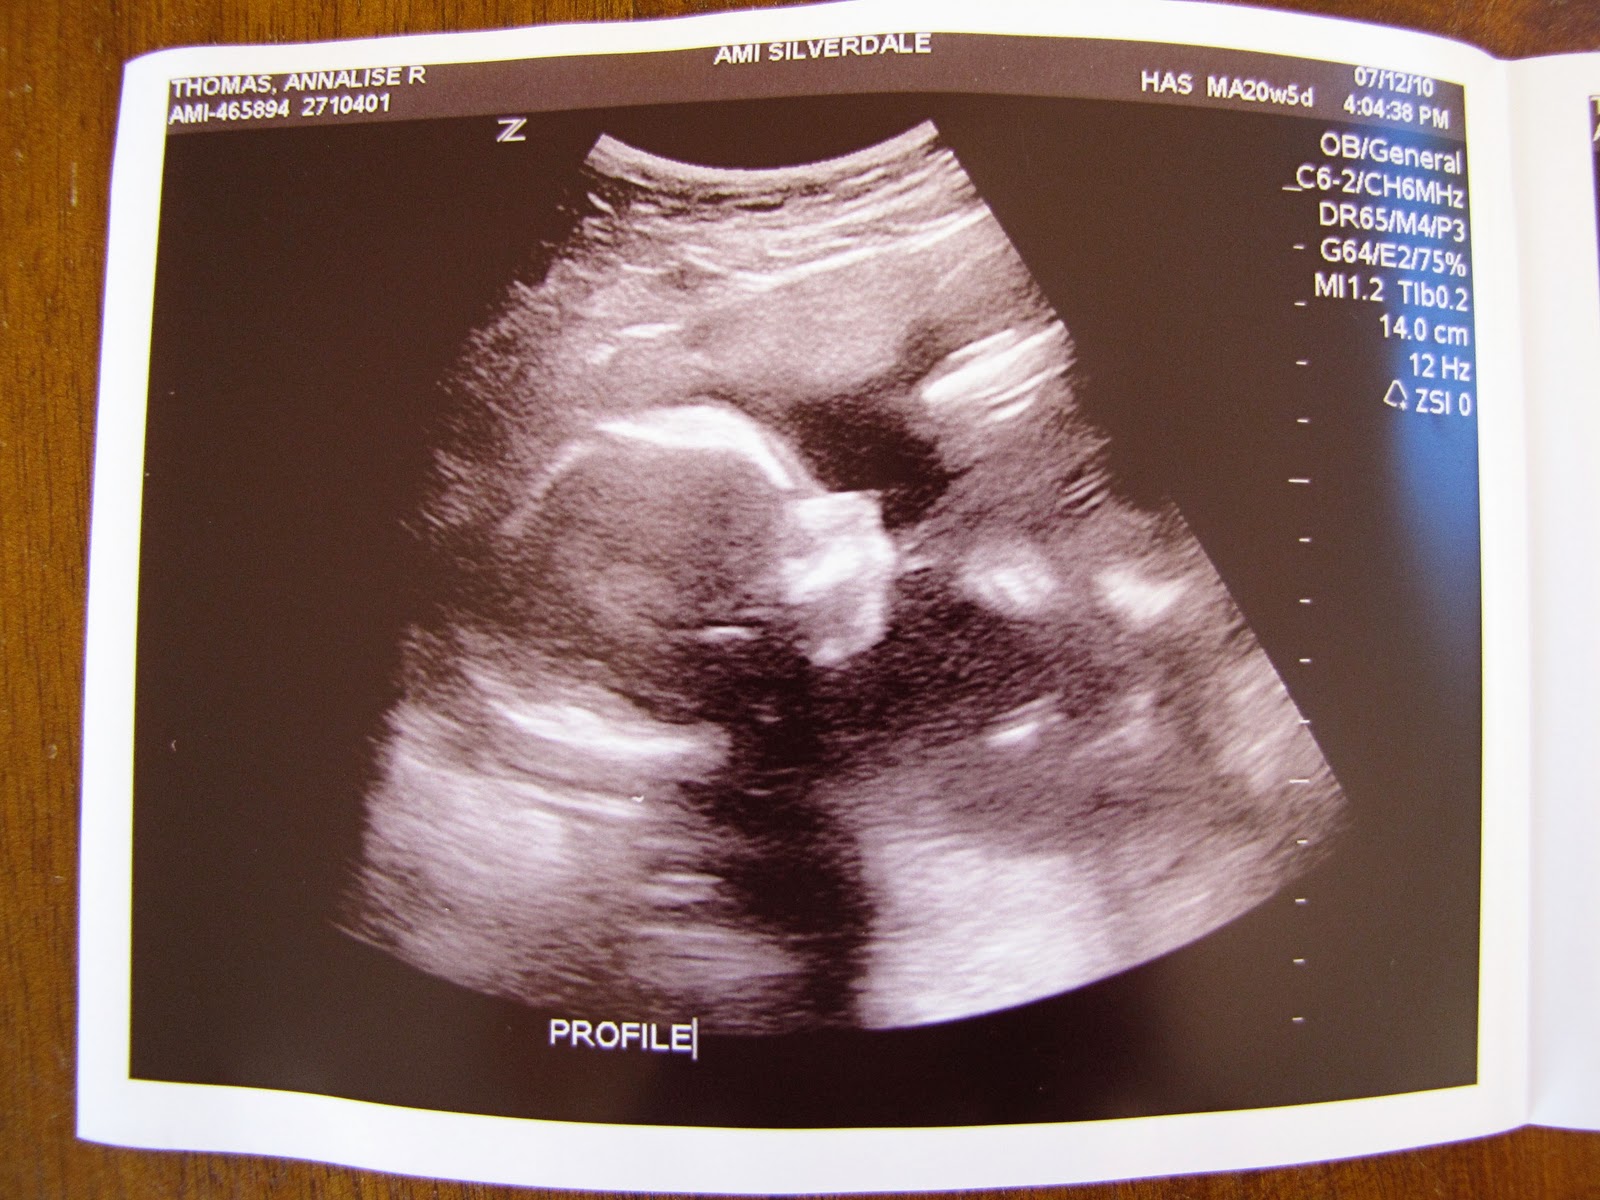

From arthomas.blogspot.com

baby boy 2's 20 weeks ultrasound! Sweet Anna's Why Is My Baby Small At 20 Weeks even having less amniotic fluid causes slow growth. Excessive exercise or dieting can also affect the baby’s nutrition causing the baby to be small. if your baby is measuring smaller than the amount of weeks you are at, they are said to have a small gestational age (via the university of rochester medical center). read the expert. Why Is My Baby Small At 20 Weeks.

From sweetannas.com

baby boy 2's 20 weeks ultrasound! Sweet Anna's Why Is My Baby Small At 20 Weeks why is my baby small? if your baby is measuring smaller than the amount of weeks you are at, they are said to have a small gestational age (via the university of rochester medical center). Most babies born from 37 weeks of pregnancy weigh between 2.5kg and 4kg. read the expert advice given to one pregnant mum. Why Is My Baby Small At 20 Weeks.